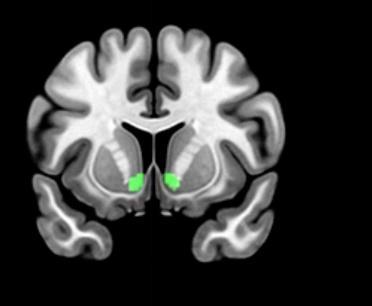

ولتوضيح هذه العملية المعقدة، تغوص هذه الورقة البحثية في أعماق بحر علم الأعصاب، وتربط بينه وبين قرارات المدراء المالية، إذ دللت الورقة على هذه العلاقة، بعدما رصد المؤلفون دليلاً على حدوث نشاط ما في الجسم المخطط البطني (Ventral striatum)، وهو جزء من الدماغ البشري يرتبط بالعواطف، حيث وجدوا ارتباطاً بين حدوث ذلك النشاط من ناحية، وبين المعلومات العاطفية التي يتلقاها المدير من ناحية أخرى، حيث يقلّ هذا النشاط في حالة المعلومات والمحفزات السلبية، مقارنة بزيادته في حال كانت هذه المحفزات إيجابية.

وخلال تصوير الأعصاب، تأخذ الورقة البحثية بعين الاعتبار القشرة الأمامية (frontal cortex) والجهاز الحوفيّ (limbic system) إلى الحد الذي يهتم به علم الأعصاب. ويُنظر إليهما على أنهما جزء من الدماغ مرتبط بعواطف البشر. أما الجسم المخطط البطني فيرتبط بشكل مباشر بعواطف الشخص سواء كانت إيجابية أم سلبية. وبالتالي تُرسل ردود الفعل العاطفية من هذا القسم من الدماغ إلى القشرة أمام الجبهية (prefrontal cortex). وهذا هو الجزء من الدماغ الذي يقوم بجمع المعلومات حول المخاطر والعواطف الشخصية الأخرى، ومن ثم ينظّم رد الفعل العاطفي في الجهاز الحوفيّ. ويتضح التفاوت في الأدمغة بشكل جلي في الخسائر أو المكاسب النقدية. وبناءً على ذلك، ثمة علاقة وطيدة بين القدرة المعرفية لمدير ما، ورد الفعل العاطفي أثناء اتخاذ قرارات مالية مختلفة.

ووثق المؤلفون تصوير ما يحدث في الدماغ بتقنية الرنين المغناطيسي الوظيفي (fMRI)، لكي يتسنى لهم فهم إمكانية استخدام علم الأعصاب فهماً كاملاً. وتُستخدم هذه التقنية لاختبار آلية عمل الدماغ أثناء اتخاذ قرارات عقلانية مرتبطة بمخالفة اشتراطات عقود الديون و إدارة الأرباح. إذ يمكن للتصوير بالرنين المغناطيسي الوظيفي تحديد المستويات المختلفة للأكسجين في الدم، وهو ما يعرف باسم التصوير المعتمد على مستوى الأكسجين في الدم (Blood Oxygen Level Dependent). ويُستخدم لتقدير نشاط الدماغ في تلك المنطقة تحت تأثير محفِّز مختلف. ولقد أدى هذا الأمر إلى الاعتقاد بأنّ النشاط في الجزء الأمامي بالجسم المخطط البطني مرتبط بالمكاسب المالية، في حين ترتبط الخسارة المالية بالجزء الخلفي على نحو أكبر. وتشير الورقة إلى أنّ ارتفاع نشاط الدماغ في الجسم المخطط البطني مرتبط بالاستجابات الايجابية و أخطاء البحث عن المخاطر، وفي المقابل يرتبط انخفاض نشاط الدماغ في الجسم المخطط البطني بالاستجابات السلبية وأخطاء تجنب المخاطر. وعلى الرغم من أنّ هذه هي الحال إلا أنه يتعذر التأكد من صحة هذه العوامل نظراً للأساليب الإشرافية المختلفة، وعدم وجود ما يكفي من الأبحاث في هذا المجال الخاص.